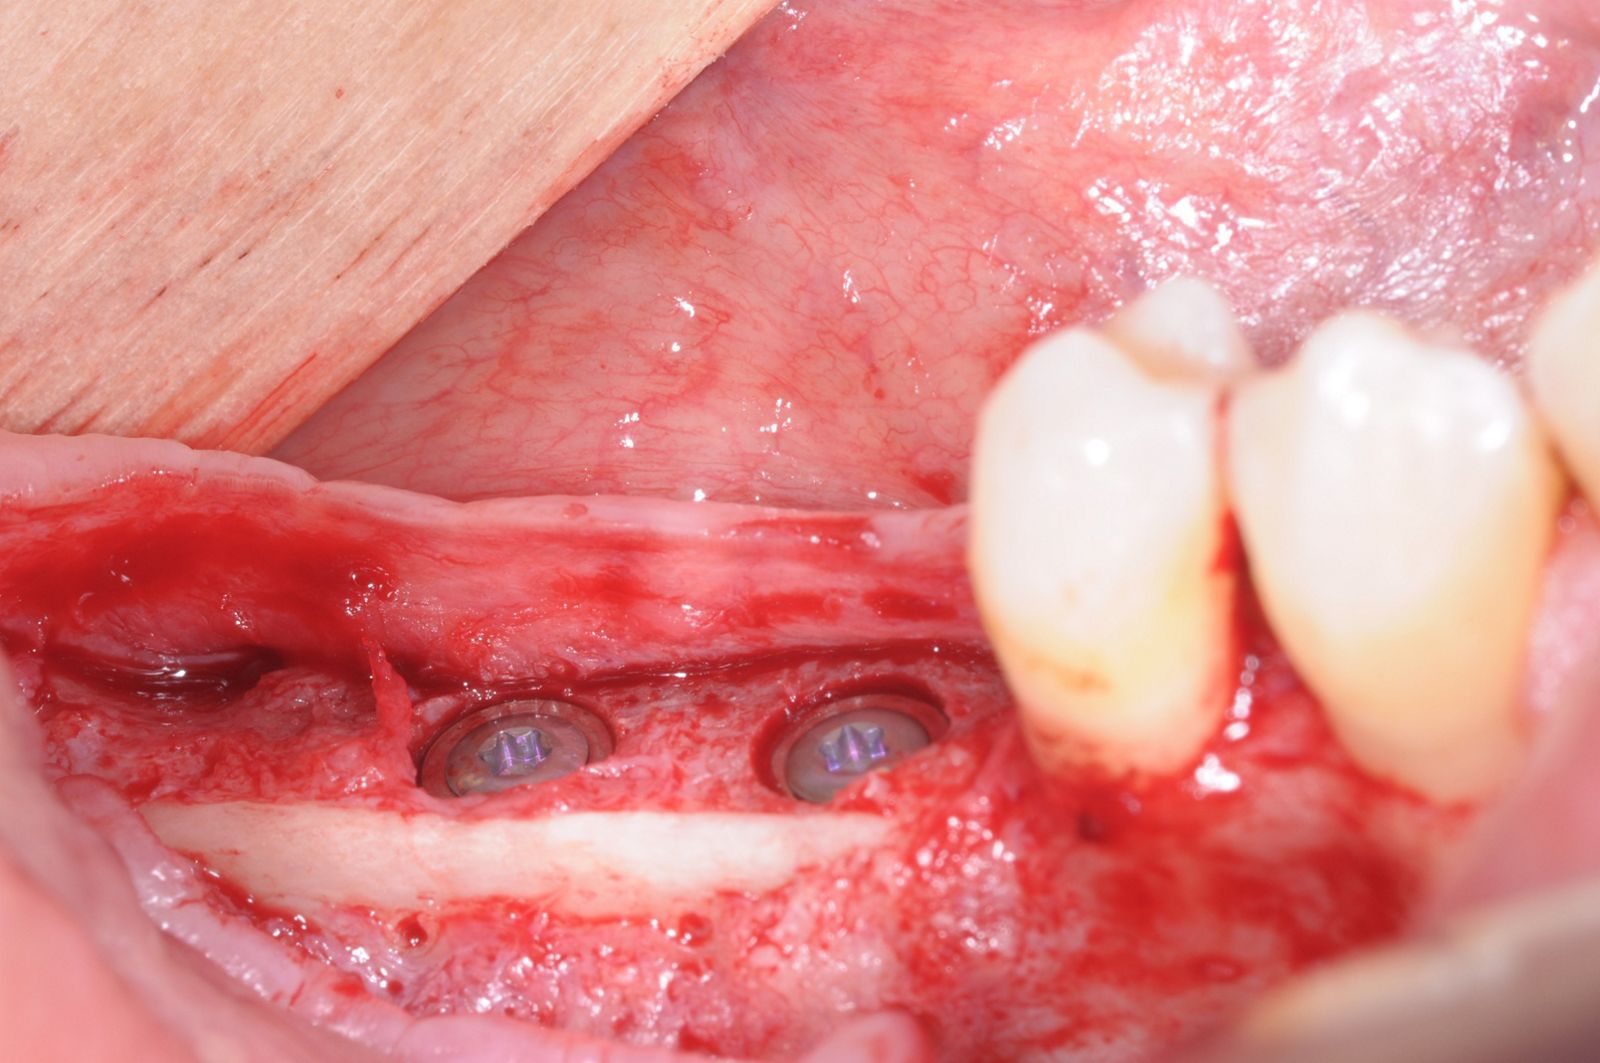

18/28 - Implantation of two Straumann BLT implants into the augmented boneThree-dimensional augmentation with maxgraft® cortico - Dr. R. Würdinger

19/28 - Placement of implant cover screws in the fully submerged dental implantsThree-dimensional augmentation with maxgraft® cortico - Dr. R. Würdinger